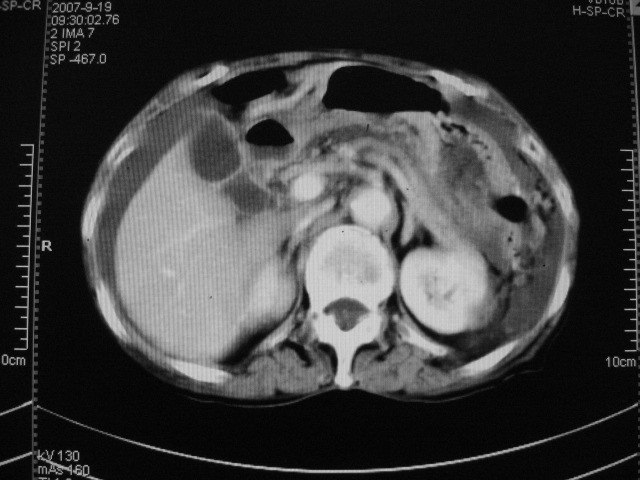

以下是引用默契在2007-9-20 17:29:00的发言:[br][br] [br] 考虑:1、胆囊占位性病变(以癌可能性大);[br] 2、中量腹水。 [br] [br]

以下是引用快乐男生在2007-9-20 15:32:00的发言:[br]图像质量不好:[br]胆囊增大,囊壁增厚,[br]可见结节突出囊腔内,[br]增强后与囊壁相仿.[br]考虑多为胆囊慢性炎症伴有胆囊体部的息肉